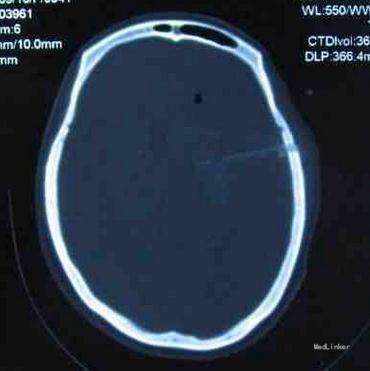

T36.7 P66次/分 R19次/分 BP160/100mmHg嗜睡状,完全运动性失语(后为混合性失语),右眼失明,左侧瞳孔正圆,对光反应灵敏,口角无歪斜,伸舌不合作,左上肢能上举,下肢能屈曲,肌张力可,右侧肢体刺激无反应,肌张力偏高,右侧Chaddock征可疑阳性,感觉,共济检查不合作。入院5日复查头CT出血量无明显变化(量约20ml),但占位效应明显,中线有移位。

入院6天行微创颅内血肿清除术。穿刺点选择(左侧OM线上6cm,距前额8cm,进针深度6.5cm)。术后3天复查头CT颅内积血已完全清除干净,予拔管,有脑脊液外渗,予头皮缝合1针。